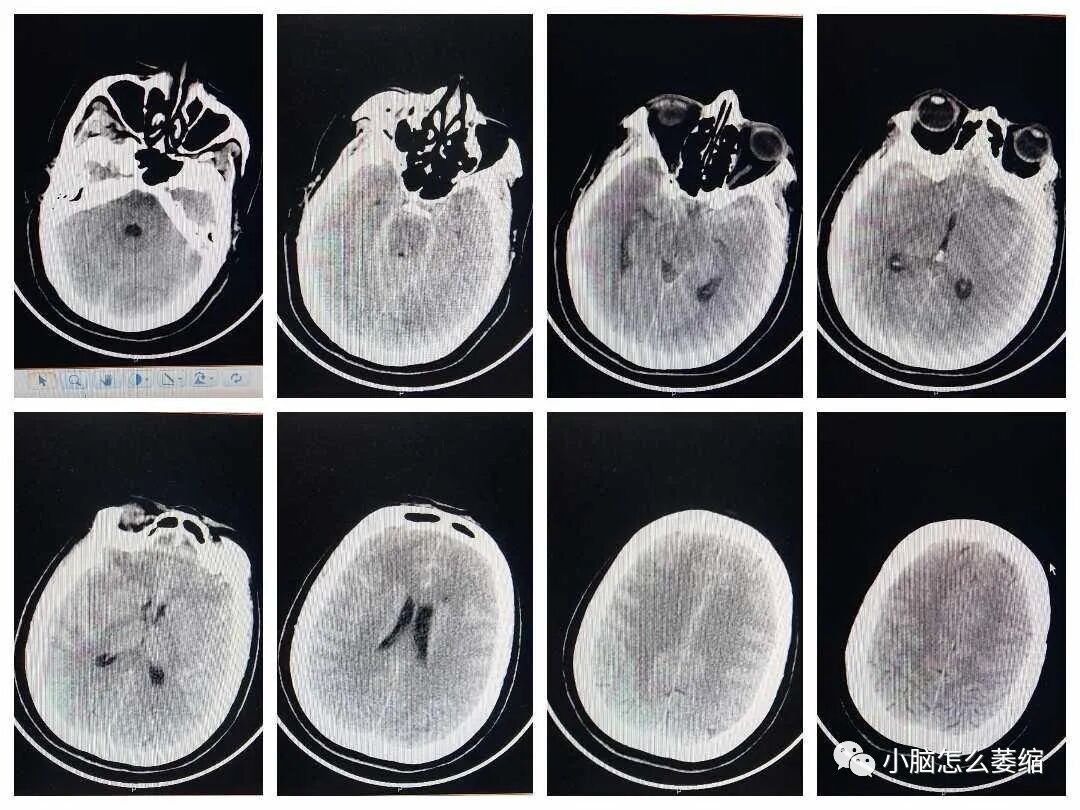

小脑萎缩是一种较为常见的神经系统疾病,患者常常出现平衡障碍、运动障碍以及语言障碍等症状。近年来,越来越多的研究关注中药在治疗小脑萎缩方面的应用。本文将介绍一例小脑萎缩患者接受中药治疗的案例,以期为小脑萎缩的治疗提供新的思路和方法。

患者张女士,今年68岁,退休教师。三年前,她开始出现明显的平衡障碍,步态不稳,且语言表达逐渐变得含糊不清。在某三甲医院确诊为小脑萎缩后,张女士开始了漫长的治疗旅程。她曾接受过西医药治疗,但副作用明显,让她苦不堪言。经过朋友推荐,张女士的治盛劲强大夫治疗小脑萎缩的效果不错,于是预约了盛大夫的面诊号位。盛大夫中医辨证为“痿证”采用补髓健脑汤加减药物治疗。

经三个疗程治疗后,呛咳次数明显减少,夜尿1-2次,大便基本正常,睡眠质量也得到了一定的改善,手凉脚凉症状没有了。经五个疗程治疗后,唐先生自主感觉比以前有力,睡眠基本正常,大喊大叫基本没有,流口水好多了。经九个疗程后说话清楚了很多,胸闷气短基本没有,所有症状均有所改善,生活质量得到了很好的提高,为巩固病情还在积极治疗当中。